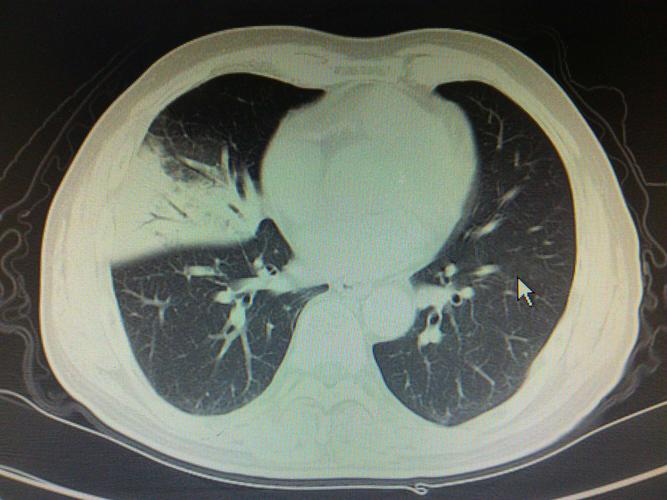

大叶性肺炎ct报告,大叶性肺炎ct

大叶性肺炎并左肺上叶肺不张,请看胸部ct结果所示

肺部大叶性肺炎ct诊断报告.docx

大叶性肺炎一例

「典型」肺炎链球菌大叶性肺炎不典型

大叶性肺炎ct

大叶性肺炎ct图片

大叶性肺炎的ct图像

大叶性肺炎ct影像图

大叶性肺炎ct影像表现

大叶性肺炎

大叶性肺炎ct典型图片

大叶性肺炎影像

大叶性肺炎图片